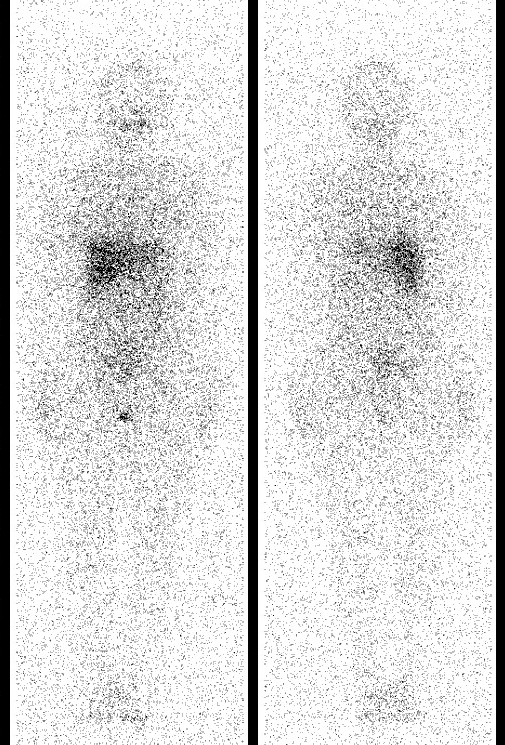

病例五 患者 女,42岁,甲状腺乳头状癌术后1月,给予治疗剂量131I 治疗后7日后,行SPECT-CT全身扫描提示:1、左颈部异常显像剂浓聚影,考虑淋巴结转移可能,摄碘良好;2、甲状腺右叶区域显像剂浓聚影,考虑少许功能性甲状腺组织显影,摄碘良好;3、双肺多处异常显像剂浓聚影,考虑甲状腺癌术后双肺多发转移可能,部分摄碘良好,建议定期随诊。半年后复查,给予诊断剂量131I口服3日后,行SPECT-CT全身扫描提示:颈部甲状腺区域及全身未见显像剂异常浓聚影

131I治疗剂量SPECT-CT全身显像 | 131I诊断剂量SPECT全身显像 |